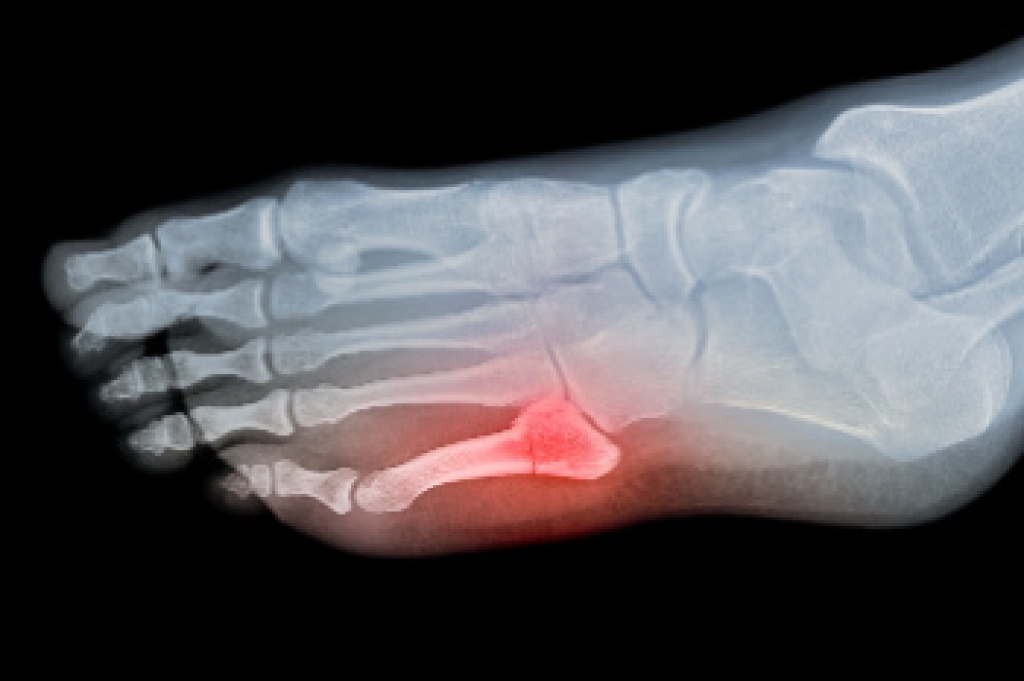

Podiatric biomechanics is a particular sector of specialty podiatry with licensed practitioners who are trained to diagnose and treat conditions affecting the foot, ankle and lower leg. Biomechanics deals with the forces that act against the body, causing an interference with the biological structures. It focuses on the movement of the ankle, the foot and the forces that interact with them.